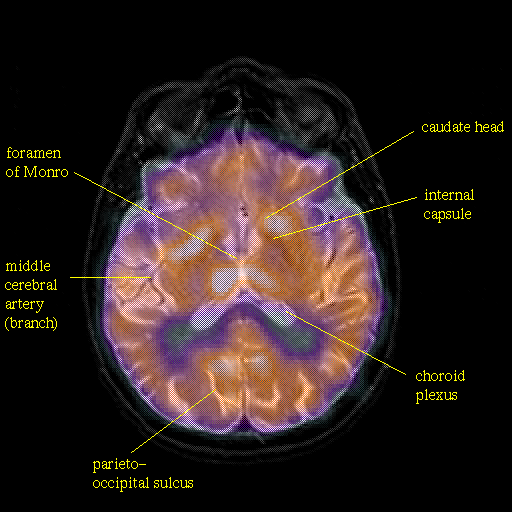

overlay: Slice 29

Slice 29

Pointers

Labeled